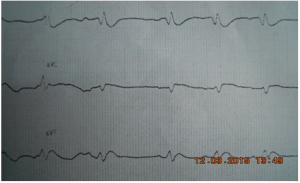

Nguyễn Thị Thanh T (NTTT), sinh năm 1990. Tiền sử bản thân và gia đình không ghi nhận có gì đặc biệt. Được cấp cứu vào bệnh viện huyện Nhà Bè thành phố Hồ Chí Minh lúc 4h30 phút trong tính trạng bất tỉnh, mạch và huyết áp không đo được. Trên monitor có rung thất, đã được sốc điện 200 J thành công. Được đặt nội khí quản bóp bóp, ghi lại điện tim và chuyển bệnh viện Nhân Dân 115 lúc 12h30 phút cùng ngày 11 tháng 3 năm 2015 trong tình trạng hôn mê.

Đầu năm 2014 chúng tôi đã đăng bài trên tạp chí về “Tái cực sớm”. Đến nay một số quan niệm về tái cực sớm đã được mở rộng hơn, một số vấn đề về tính di truyền… đã có những phát hiện hé mở.

Mẫu ER

Tỷ lệ tương đối cao của mẫu ER trong dân số chung (5-13%) so với tỷ lệ VF tự phát (khoảng 10 trường hợp trên 100.000 dân), mẫu ER hầu như luôn luôn là những nhận định lành tính ngẫu nhiên của ECG. Không có dấu hiệu cụ thể hoặc các triệu chứng được quy cho mẫu ER, được xác định bằng cách sử dụng một ECG tiêu chuẩn. Nếu không có ngất hoặc đột tử do tim, thì không có test nào đòi hỏi cho người có mẫu ER.

Thuật ngữ tái cực sớm (early repolarization: ER), cũng được hiểu như “sóng J” hoặc “điểm J chênh lên”, từ lâu đã được sử dụng để mô tả một biến thể QRS -T trên điện tâm đồ (ECG).Hầu hết các tài liệu xác định ER như có mặt trên điện